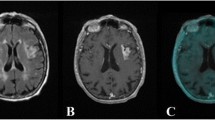

Imaging findings of patient #1 diagnosed with PACNS. Coronal T1wi after Gadovist® injection demonstrates the two major contrast enhancing lesion in the left putamen and left temporal lobe (a, c, arrows, contrast-enhanced MRI 2 weeks before PET scan). Coronal FLAIR/PET overlay demonstrates [18F]DPA-714 uptake of the lesions (b, d) with additional regional tracer uptake of the left corticospinal tract. (e) Tractography images overlaid with T1wi demonstrate reduced left sided fiber integrity. Follow-up FLAIR/PET, 4 weeks after induction of anti-inflammatory therapy, (f) demonstrates normalization of uptake in the left temporal lesion and constant uptake of the left corticospinal tract

We performed a follow-up [18F]DPA-714 scan in patient #1 4 weeks after anti-inflammatory treatment initiation with high-dose intravenous corticosteroids to examine the changes in inflammation and immune cell infiltration. In this scan, pathologic [18F]DPA − 714 uptake in the temporal lesion was no longer visible (SUVmax L/C: 1.05 vs 1.3 at baseline), whereas the initial regional uptake of the left corticospinal tract remained unaltered (SUVmax L/C: 1.2 vs 1.2 at baseline, Fig. 1 f).

A 60-year-old female patient was hospitalized with disorientation and declined psychomotor performance indicating relapse of previously diagnosed PACNS. PET-MRI 4 days after corticosteroid therapy initiation showed a widespread increased cerebral uptake of [18F]DPA-714 in the whole right cerebral hemisphere (Fig. 3). In this case, tracer influx varied between the cerebral and cerebellar hemispheres as a result of the heavily impaired perfusion due to large arterial vessel involvement (Fig. 3 f, g). Tracer uptake of the two cerebellar hemispheres converged over time; however, tracer uptake in the cerebral hemispheres continuously diverged with higher uptake in the right hemisphere putatively reflecting increased TSPO binding. Tracer uptake was especially elevated at the right occipital pole where diffusion restriction was apparent in DWI and ADC mapping indicating subacute ischemia (SUVmean L/C: 1.6, Fig. 3 a-c). Another subacute infarction at the right splenium with extensive edema (Fig. 3 d, e) did not show particularly increased tracer accumulation compared to the overall elevated uptake of the right hemisphere (SUVmean L/C: 1.2).

Imaging findings of patient #2 diagnosed with PACNS. [18F]DPA-714-PET images fused to FLAIR demonstrate elevated tracer uptake of the whole cerebral hemisphere. Right-sided occipital pole hotspot (b, arrow FLAIR/PET overlay, c, PET) corresponds to diffusion restriction as indicated by DTI (a, white arrow, MR scan 5 days before PET/MRI). FLAIR image of subacute ischemia in the right splenium (d, white arrow) corresponding to fusion image (e). Coronal T1wi after contrast agent application demonstrates vessel wall uptake (f, white arrows, contrast-enhanced MR scan 5 days before PET/MRI). (g) Time activity curves of symmetric ROIs on the occipital / temporal cortices and symmetrical spherical VOIs on the cerebellar hemispheres as indicated in the inset images